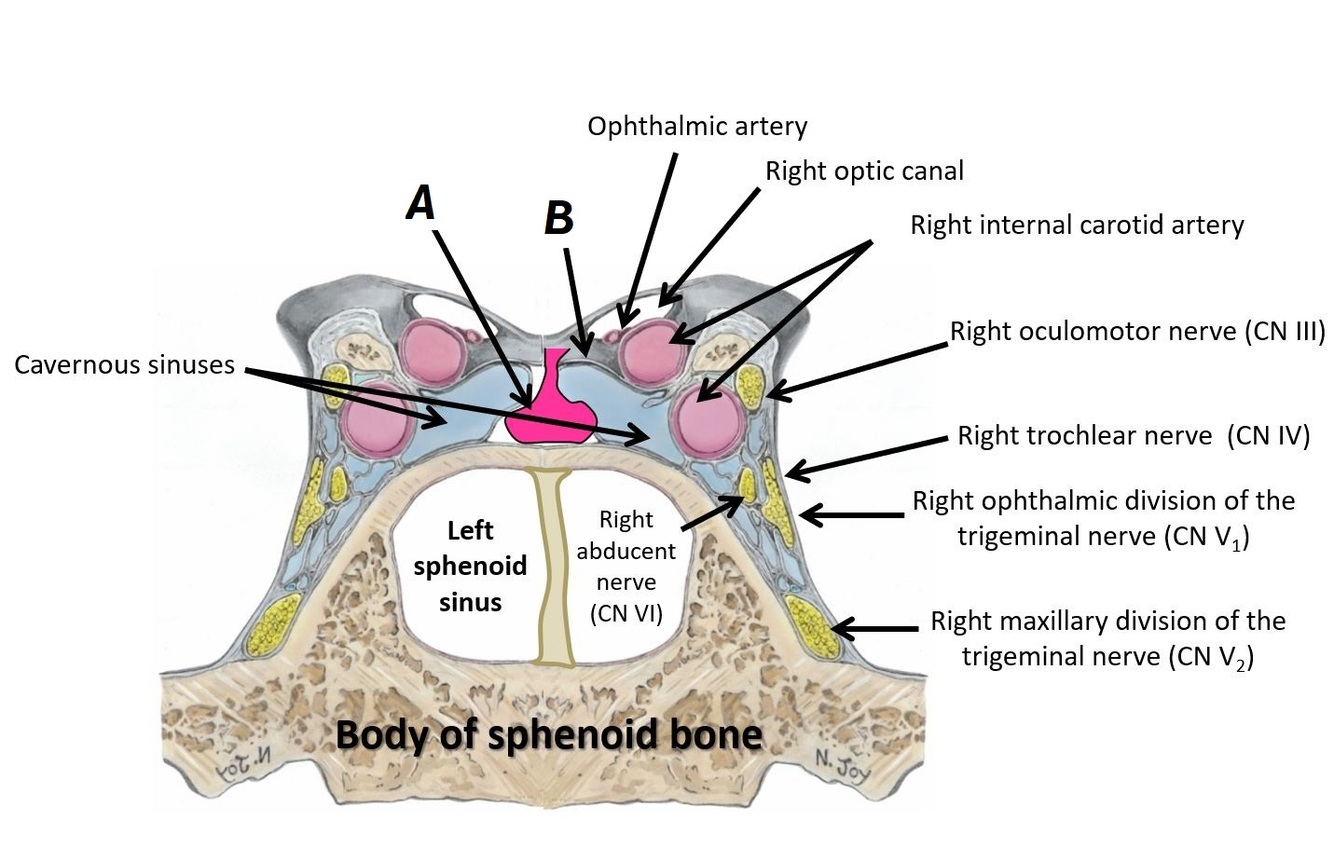

Name structures A, B and C

A - Opthalmic artery

B - Right optic canal

C - Right internal carotid artery